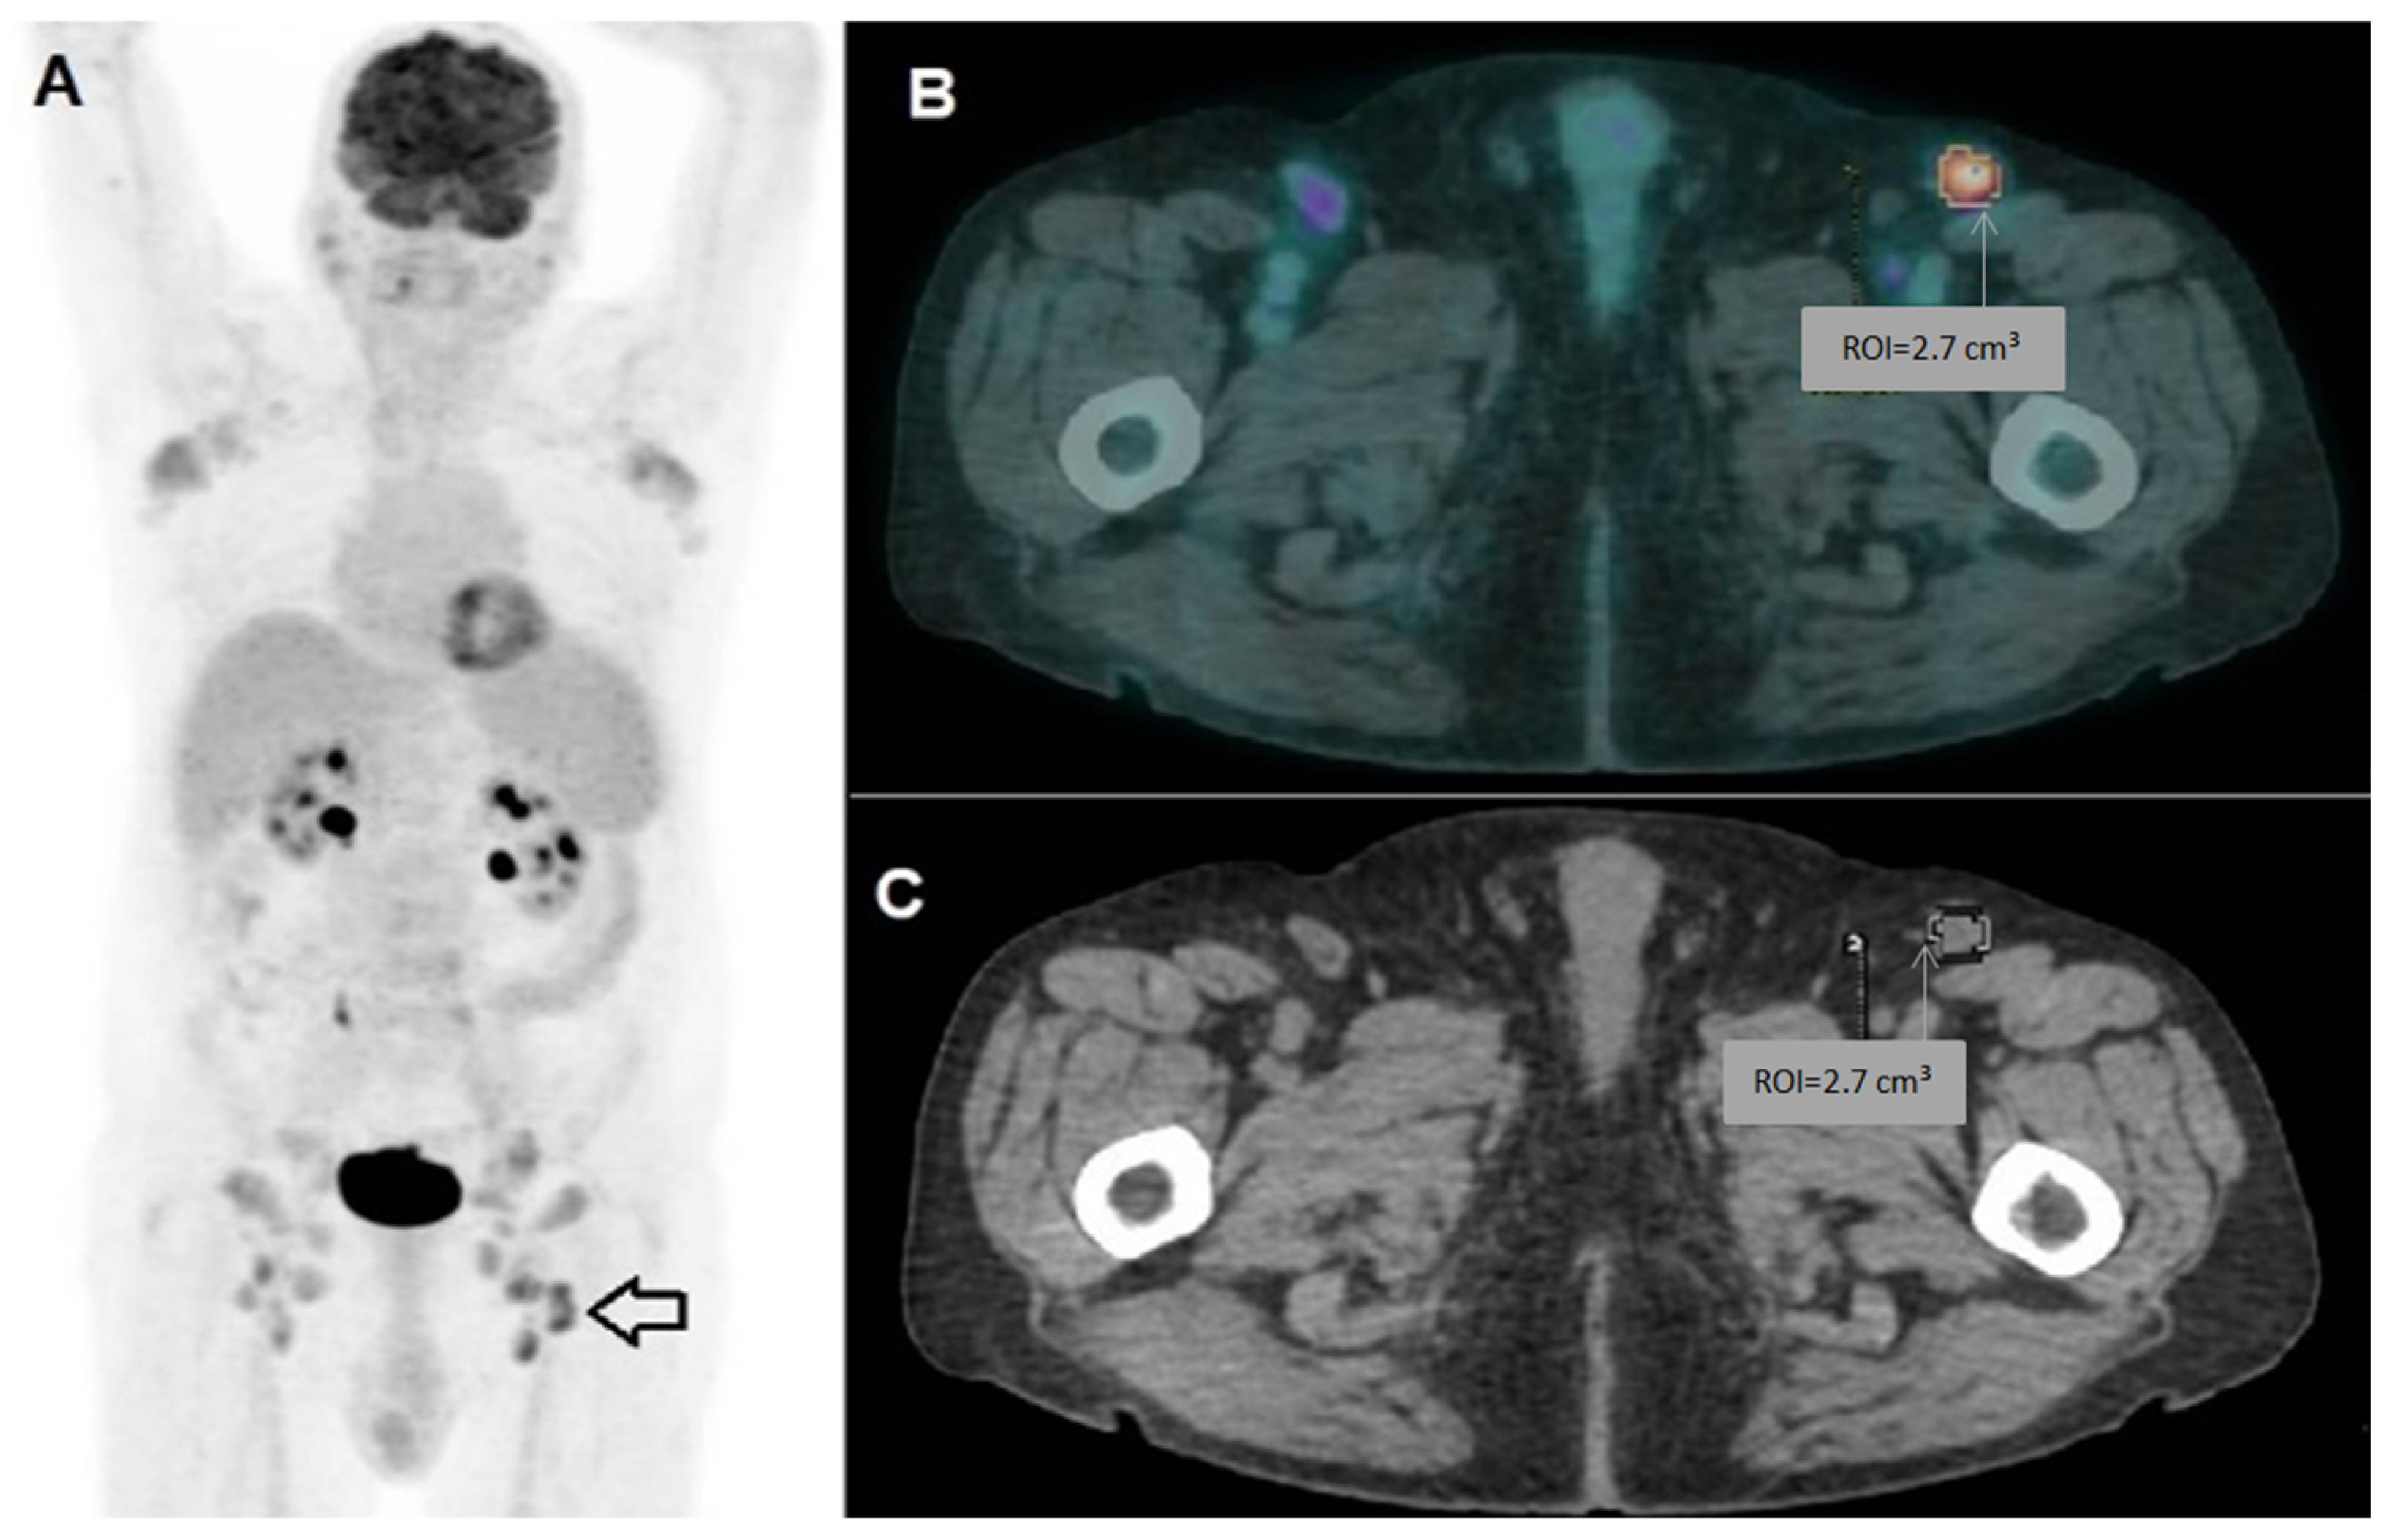

2.2. Image Acquisition and Analysis

2.3. Radiomic Workflow

3.2. Radiomic Analysis